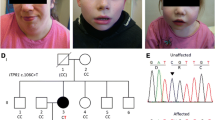

Neurological characteristics of SCAIS include a wide-based stance, spinocerebellar ataxia characterised by thoracic limb hypermetria (hyperextension), pelvic limb hyperflexion, truncal swaying, impaired balance, pendular nystagmus and absent menace response bilaterally. The remainder of the neurological examination was within normal limits. As the disease progressed intentional head tremor was observed and balance impairment deteriorated to the point that the dogs were unable to stand up and ambulate at approximately 1 year of age. Haematology, serum biochemistry and urinalysis were unremarkable in all affected dogs. MRI of the brain of two affected 8-month-old littermates (one male and one female) showed a subjective mild increase in sulcal widths and exaggerated definition of the folia in the rostral lobe of the cerebellum, suggesting grey matter loss. In addition, a cerebellar vermian defect was noted in the ventral portion of the cerebellum. However, these MRI changes were observed also on MRI of a clinically normal female littermate unaffected by the ITPR1 mutation, and therefore their clinical significance remains dubious. MRI was repeated in the affected female dog 5.5 weeks after the first one; however, no changes were observed despite significant clinical deterioration. MRI of the cervical spine revealed no abnormalities in the two IS undergoing cervical MRI. The clinically normal individual subjected to MRI was followed up for several years by a veterinary neurologist and did not develop any clinical signs of spinocerebellar ataxia. The MRI results therefore cannot be seen as diagnostic of SCAIS and may just have shown mild anatomic variants of no clinical significance. Cisternal cerebrospinal fluid (CSF) analysis was normal (in four tested dogs) and CSF PCRs for canine distemper virus, Toxoplasma gondii and Neospora caninum were negative (in two tested dogs). Brain stem auditory evoked response testing was normal (in four tested dogs).

Long range PCR was used to confirm expansion of the region in cases. Amplification was only achievable using highly intact genomic DNA, meaning no results could be obtained for 6 of the 13 cases for which DNA was obtained from FFPE brain tissue. The seven remaining cases all had two expanded alleles, although none of the cases had two alleles of identical length even though the cases were all homozygous for an identical disease-associated haplotype which is indicative of a founding expansion event. Allele size ranges are demonstrated in Fig. 3. Expanded alleles were estimated to range from 318 to 651 GAA repeats in length (Supplementary File 2). All 15 obligate carriers in our sample collection were heterozygous for the repeat expansion, with non-expanded alleles ranging from approximately 7–22 subunits. Both intergeneration expansion and reduction in repeat copy number were observed. The expansion was confirmed as a pure GAA repeat expansion by Sanger sequencing of a gel extracted case allele amplicon (Fig. 4).

We have identified a GAA repeat expansion in intron 35 ITPR1 which is strongly associated with autosomal recessive SCAIS. Cases in the study had expanded alleles in the range of approximately GAA(300) to GAA(650) in comparison to a wild-type range of GAA(7) to GAA(22). All cases shared a common disease-associated haplotype, but had two expanded repeat alleles of varying length, implying that repeat length is unstable and generational expansion and contraction was observed.